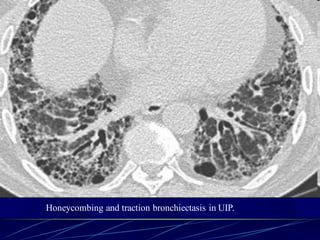

HONEYCOMBING

Defined as - small cystic spaces with

irregularly thickened walls composed of

fibrous tissue.

Predominate in the peripheral and subpleural

lung regions

Subpleural honeycomb cysts typically occur

in several contiguous layers. D/D- paraseptal

Honeycombing is defined by the presence of small cystic

spaces with irregularly thickened walls composed of

Causes

Lower lobe predominance :

1. UIP or interstitial fibrosis

2. Connective tissue disorders

3. Asbestosis

4. NSIP (rare)

Upper lobe predominance :

1. End stage sarcodosis

2. Radiation

3. Hypersensitivity Pneumonitis

4. End stage ARDS

140

Honeycombing and traction bronchiectasis in UIP.

Typical UIP with honeycombing and traction

bronchiectasis in a patient with idiopathic

pulmonary fibrosis (IPF)